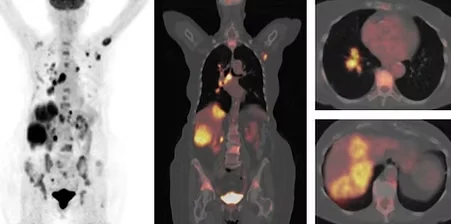

PET/CT Scans

PET/CT scans utilize a radiotracer to obtain both physiologic and anatomic information. The radiotracer used (FDG, Gallium-68 Dotatate, Axumin, Neuraceq, Amyvid, etc.) varies based on the patient's indication and on the specific PET/CT scan ordered by the patient's referring physician.